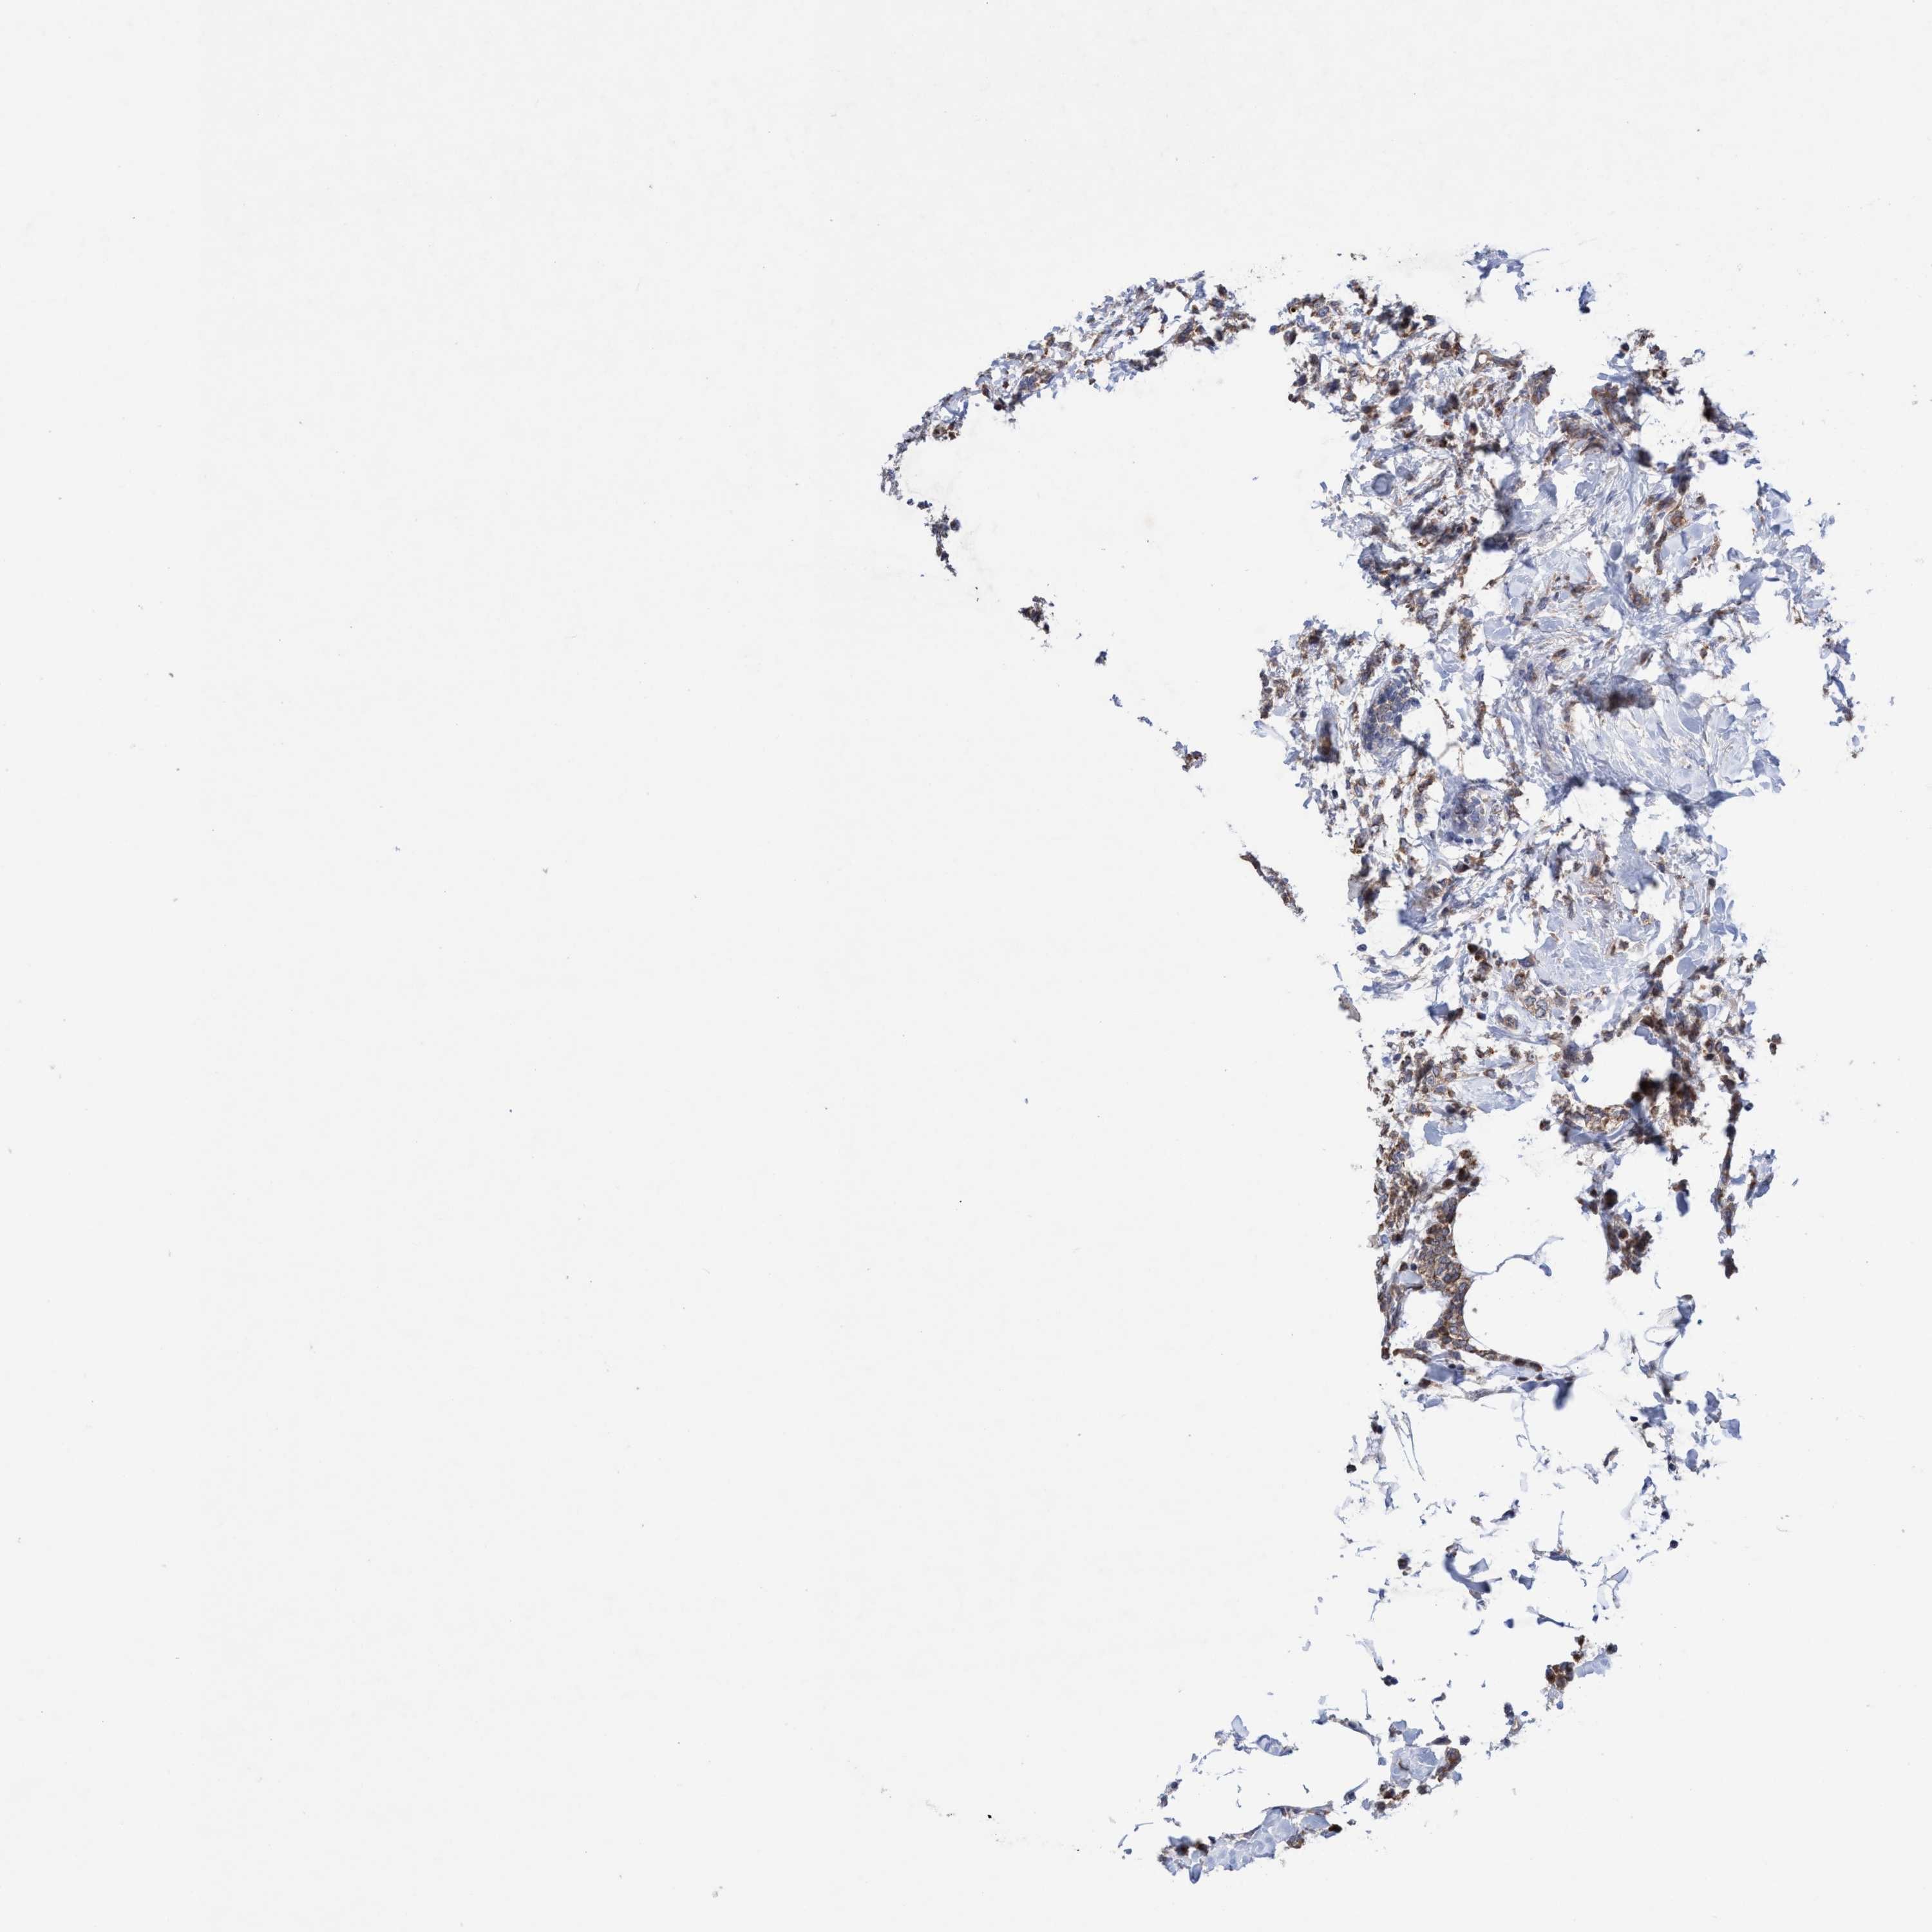

BRCA TCGA BRCA VALIDATION PROTEIN EXPRESSION

ANTIBODIES

AND

VALIDATION